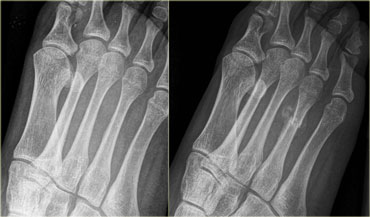

Stress fracture of 4th metatarsal: Radiograph at presentation and at 3 weeks follow up. Stress fracture of 4th metatarsal: Radiograph at presentation and at 3 weeks follow up.

Metatarsal bones

The metatarsal bones are common sites for stress fracures (25% of stress fractures).

On the left a 15-year old female with no history of trauma.

Recent onset of lateral forefoot pain with walking.

The radiograph taken at presentation is unremarkable.

Follow-up at 3 weeks shows complete fracture of the distal shaft of the 4th metatarsal with overt periosteal reaction

Stress fracture of 2th metatarsal: Radiograph at presentation and at 1 and 3 months follow up. Stress fracture of 2th metatarsal: Radiograph at presentation and at 1 and 3 months follow up.

On the left a 39-year old female with forefoot pain which began during a biking holiday. The radiograph at presentation is normal.

At 1 and 3 months follow-up, clear healing tendencies can be seen, indicating the presence of a stress fracture